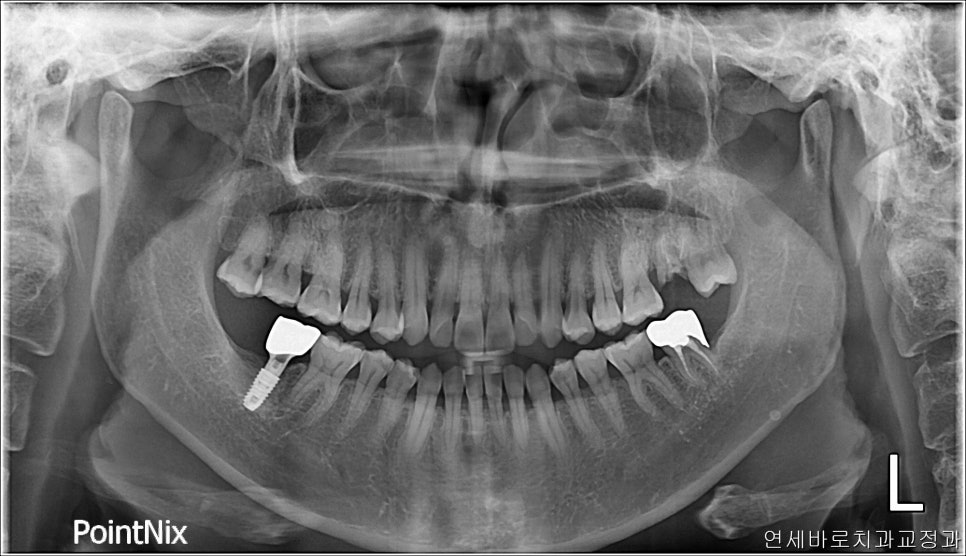

이쪽 부분에 임플란트를 심고 싶어서 오셨던 분입니다.

긴 상담 끝에 임플란트를 안하고, 뒤에 있는 사랑니를 1)돌리고 2)올리고 3)당겨오기로 했습니다

사실 위치도 안좋고, 시간은 오래걸릴것같긴했지만